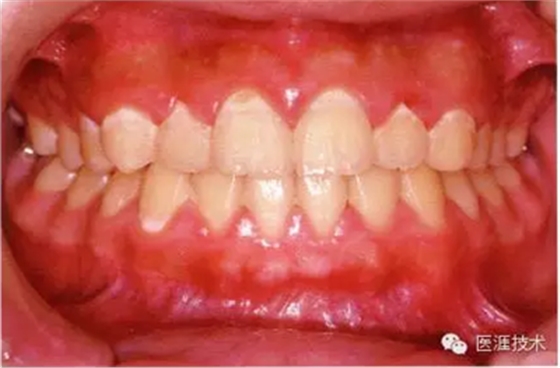

26歲男性牙齦炎的臨床圖像

26歲男性。開口呼吸。混合有牙齦發(fā)紅、腫脹與纖維性肥厚。菌斑干燥牢牢黏住,刷牙難以刷掉。